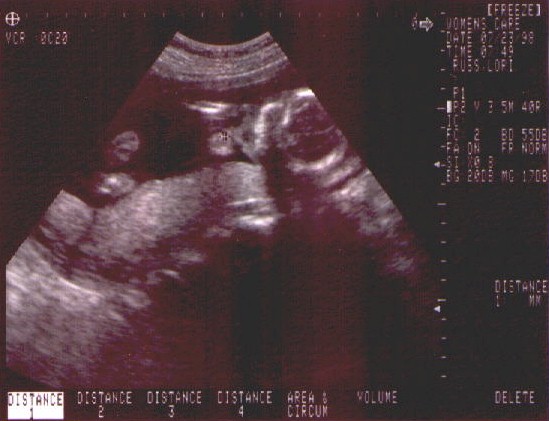

• 23rd July 1998 - Second and final ultrasound today (if nothing goes wrong).  We got to see a healthy developing baby girl.  Brain, heart, skeletal and organ development is on track and looking good.  We decide on the name for sweet pea - Caitlin Elizabeth Russ.  Take a look at the sonograms we have from the ultrasound.

Click here for full size picture!

Little Caitlin's Profile